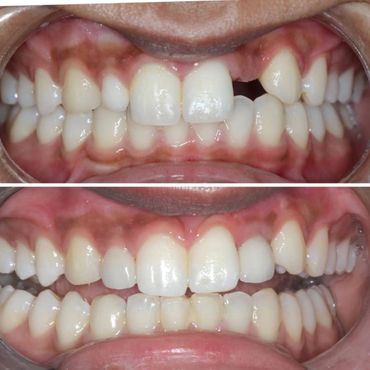

When natural teeth are lost, the face begins to show signs of aging due to bone loss. If you wait too long, the food chewing muscles begin to shorten to accommodate the reduced space between your nose and your chin. Missing one or more teeth could affect the overall health of the surrounding teeth and gums. A dental Implant is the solution to stop bone loss and restore the facial skeletal structure.

2. Restore normal facial aesthetics

5. Increased confidence